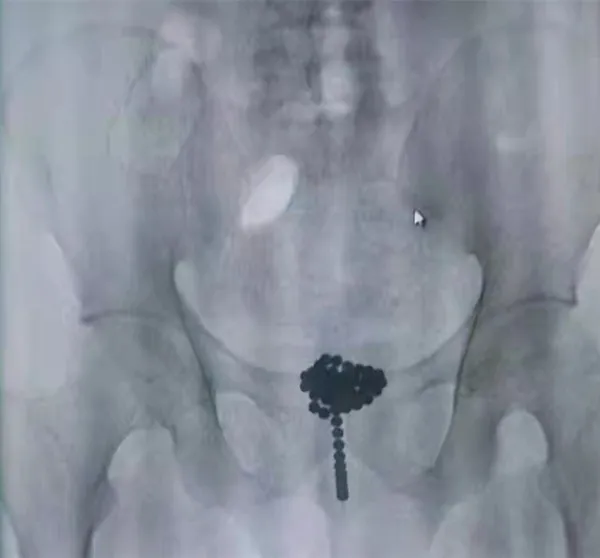

经过X光和CT检查显示,65颗直径8毫米的磁力珠成团滞留在尿道及膀胱内。

考虑到异物被塞入体内已超过24小时,堵塞尿道和膀胱,病人痛苦不堪,另外磁力珠腐蚀性很大,时间长了会导致膀胱穿孔,造成严重后果。

手术在全麻下进行,由于磁力球表面光滑,球体炫彩,反光明显,对手术干搅极大,加之磁力球已吸附成团,取石钳夹取困难。

经过一个多小时 ,曹建波手术团队终于将65颗磁力珠全部成功取出。